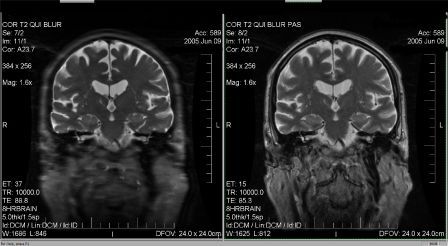

Tu as raison de préciser Higgins que ce n'est pas l'artéfact de troncature... Cet artéfact est dû à une trop grande différence de pondération entre le TE effectif (TE eff) qui va coder pour les lignes centrales de l'espace de Fourier et la pondération du dernier écho du train d'échos (TE max) qui lui, va coder les lignes périphériques de l'espace K. Dans l'exemple ci-dessous, vous pouvez trouver une image volontairement mal paramétrée pour créer du blurring (Train d'écho trop grand) et une image optimisée (paramètres réglés pour que le TE effectif soit au centre du train d'échos). Cet artéfact est souvent confondu avec l'artéfact de mouvement ou est souvent pris pour une mauvaise résolution spatiale...

Pièces jointes : |

blurring anonyme.jpg [ 25.21 Kio | Consulté 49932 fois ]